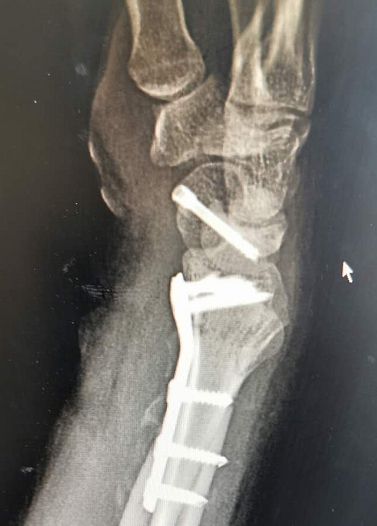

据骨科吴主任介绍

经过检查发现

小李的左桡骨远端粉碎性骨折

左腕舟骨骨折、腰椎骨折

随后,吴主任为小李进行了

左桡骨远端粉碎性骨折

左腕舟骨骨折切开复位内固定手术